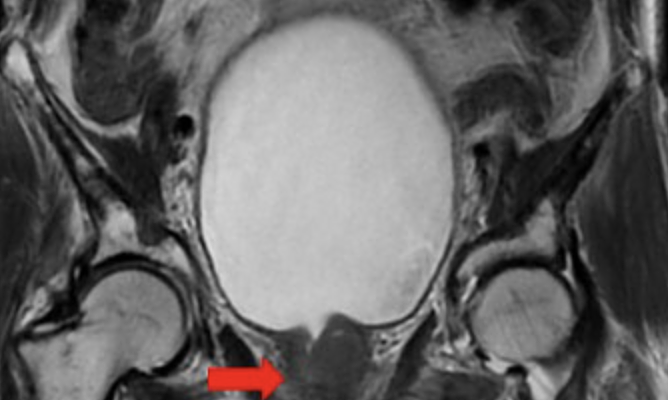

Kết quả chụp cộng hưởng từ cột sống ngực phát hiện nhiều tổn thương vùng ngực, đốt sống, tuyến tiền liệt. Bác sĩ chẩn đoán bệnh nhân ung thư tuyến tiền liệt di căn xương, hạch, giai đoạn 4 kèm bệnh gout, đái tháo đường type hai.